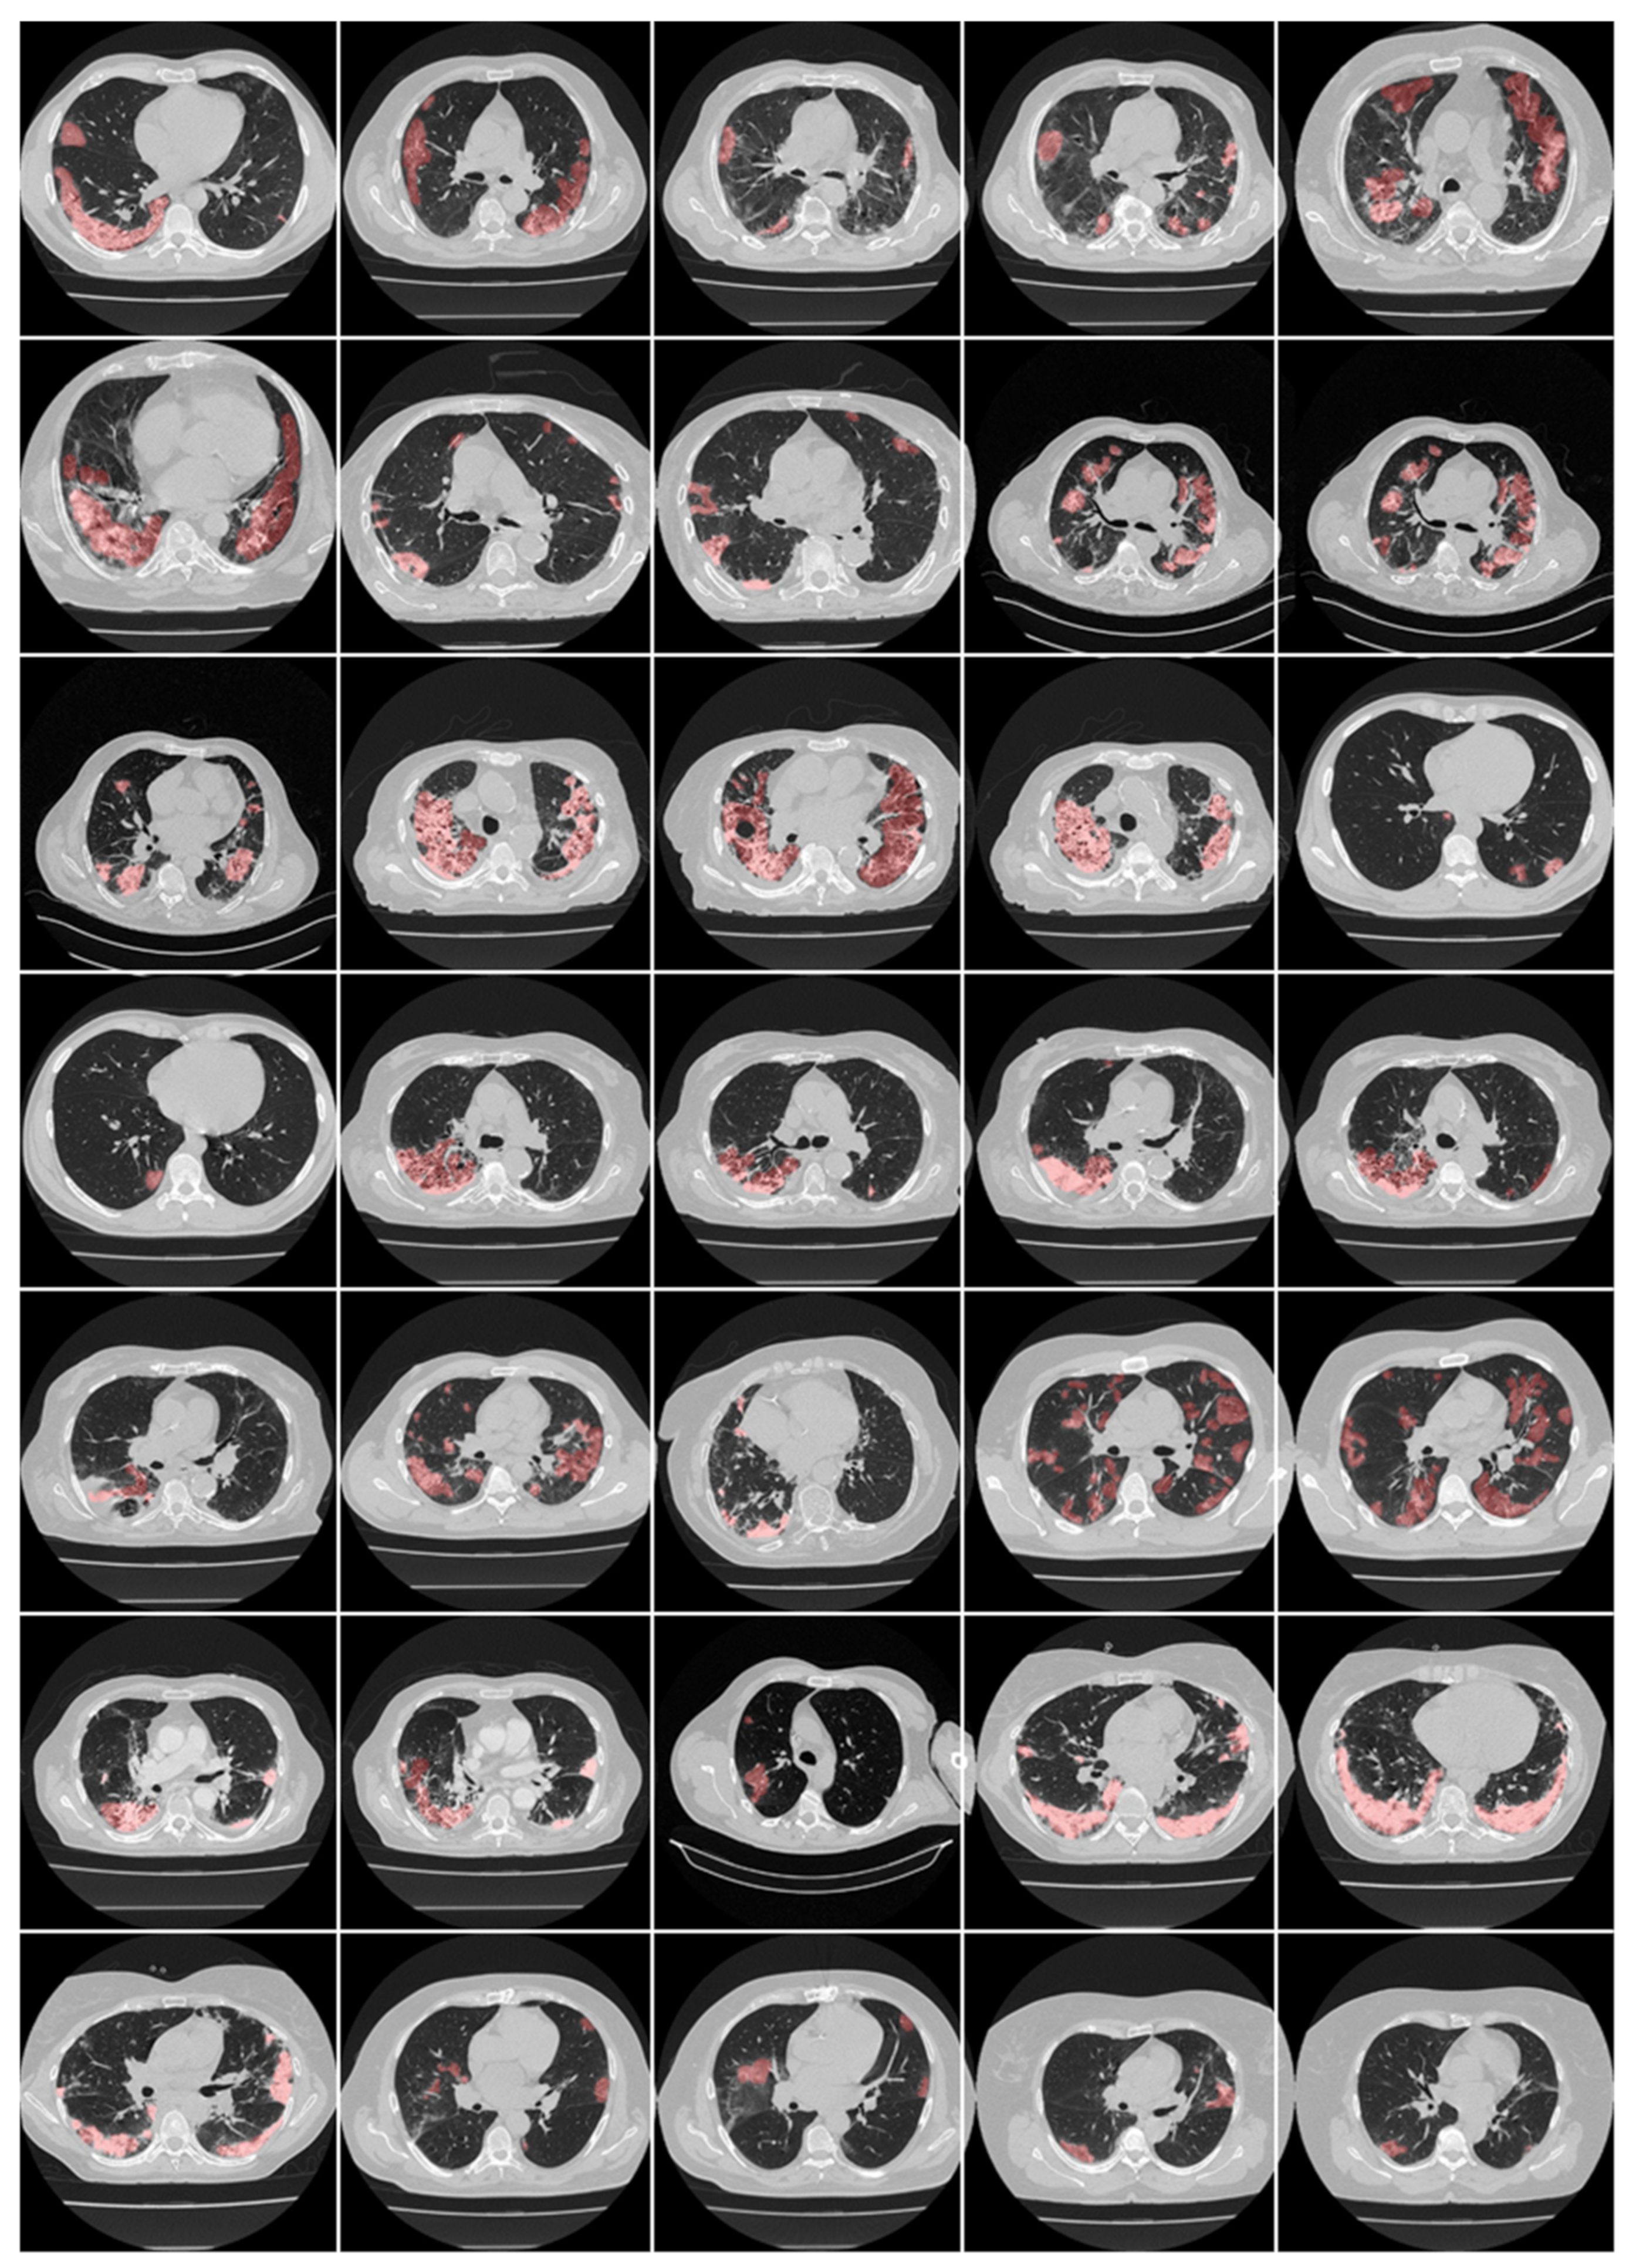

Here, we focus on CT-based lung lesion segmentation and its quantification, which acts as a covariate (or feature) during the DL paradigm. In DL, manual delineations of CT lung lesions are challenging and are also vital for the design of offline DL training models. Figure 12 and Figure 13 illustrate the highlighted COVID-19 lesions in CT lungs using manual delineation by experienced tracer 1 and 2, respectively. This is shown in the red color lesion as an overlay image with a grayscale CT image in the background. When it comes to COVID-19 lung lesion detection and quantification in CT, Suri et al. [217,218] have demonstrated the usage of hybrid DL (HDL) models vs. solo DL (SDL) models, exhibiting its superiority for lung lesion segmentation in CT scans. One of the most important aspects of DL is the optimization of hyperparameters during training to obtain the best performance of the DL system. It thus requires optimizing, (i) learning rate, (ii) number of epochs, (iii) batch size, and (iv) batch normalization, and (v) adding dropout layers to prevent overfitting and obtain generalization. Further, to achieve the best DL design, one must use several sources of biomarkers with a different set of data sources in a large amount in a big data framework, ensuring a multiresolution framework for faster execution time [202]. Transfer learning can also be used in CT lesion segmentation for transferring the knowledge between models, so-called pretrained models, ensuring higher speed [150,219]. Table 4 shows a variety of pretrained DL models such as DenseNet 201, ResNet50 V2, MobileNet, and VGG-16. SegNet and UNet models are stronger than the CNN models. The ResNet50 V2 model has higher accuracy compared with the 3-layer CNN and VGG-16 networks.